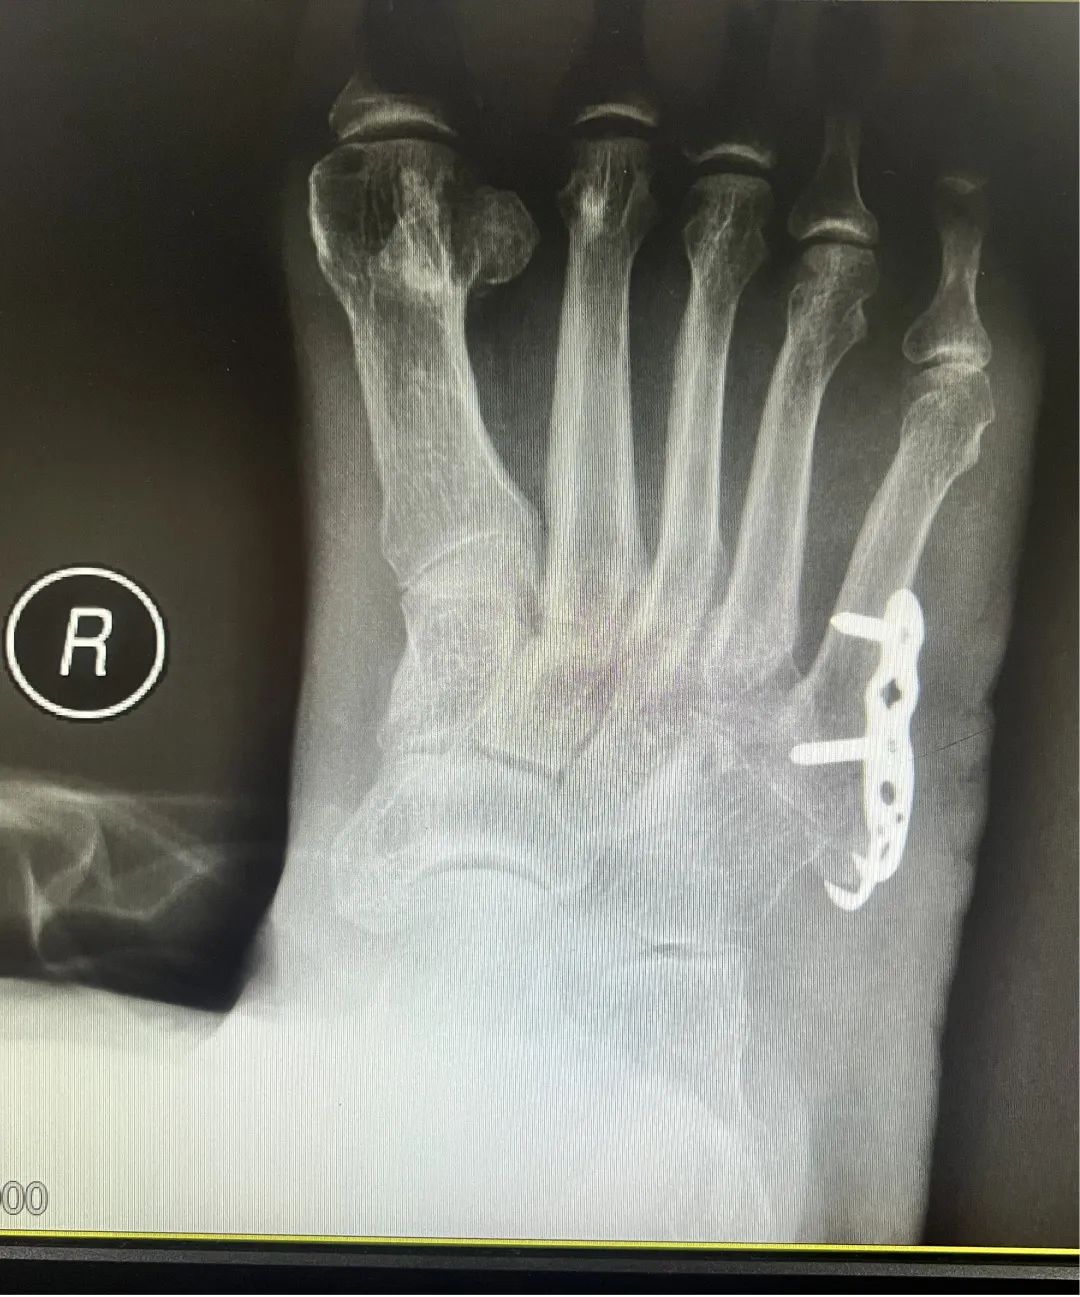

于是,隆奶奶在家人的陪同下到云南省中医医院滇池院区风湿科就诊。入院后风湿病科主治医生针对患者情况为患者进行了检查,X片显示:患者右足第五跖骨基底部骨折。于是风湿科主治医生为患者请了骨四科李智奎副主任医师会诊。经骨科专家会诊后,综合诊治隆奶奶的情况,建议隆奶奶手术治疗。

2022年2月25日,隆奶奶转入骨伤科四病区继续治疗,接诊的李智奎副主任医师及王清医生为隆奶奶完善相关术前检查,于当日下午为其实施了右足第五跖骨基底部骨折切开复位内固定术,隆奶奶术后恢复良好。右足骨折的问题解决了,但隆奶奶颈部疼痛、双上肢麻木疼痛的问题仍然没有缓解。因为右足的手术治疗,隆奶奶及家人对骨伤科四病区医护人员的医术及服务非常信任和满意,于是听从医生的建议,决定手术治疗。